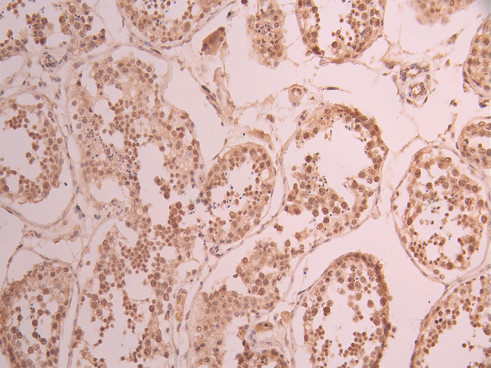

IHC image of CSB-RA293843A0HU diluted at 1:100 and staining in paraffin-embedded human testis tissue performed on a Leica BondTM system. After dewaxing and hydration, antigen retrieval was mediated by high pressure in a citrate buffer (pH 6.0). Section was blocked with 10% normal goat serum 30min at RT. Then primary antibody (1% BSA) was incubated at 4°C overnight. The primary is detected by a Goat anti-rabbit polymer IgG labeled by HRP and visualized using 0.05% DAB.